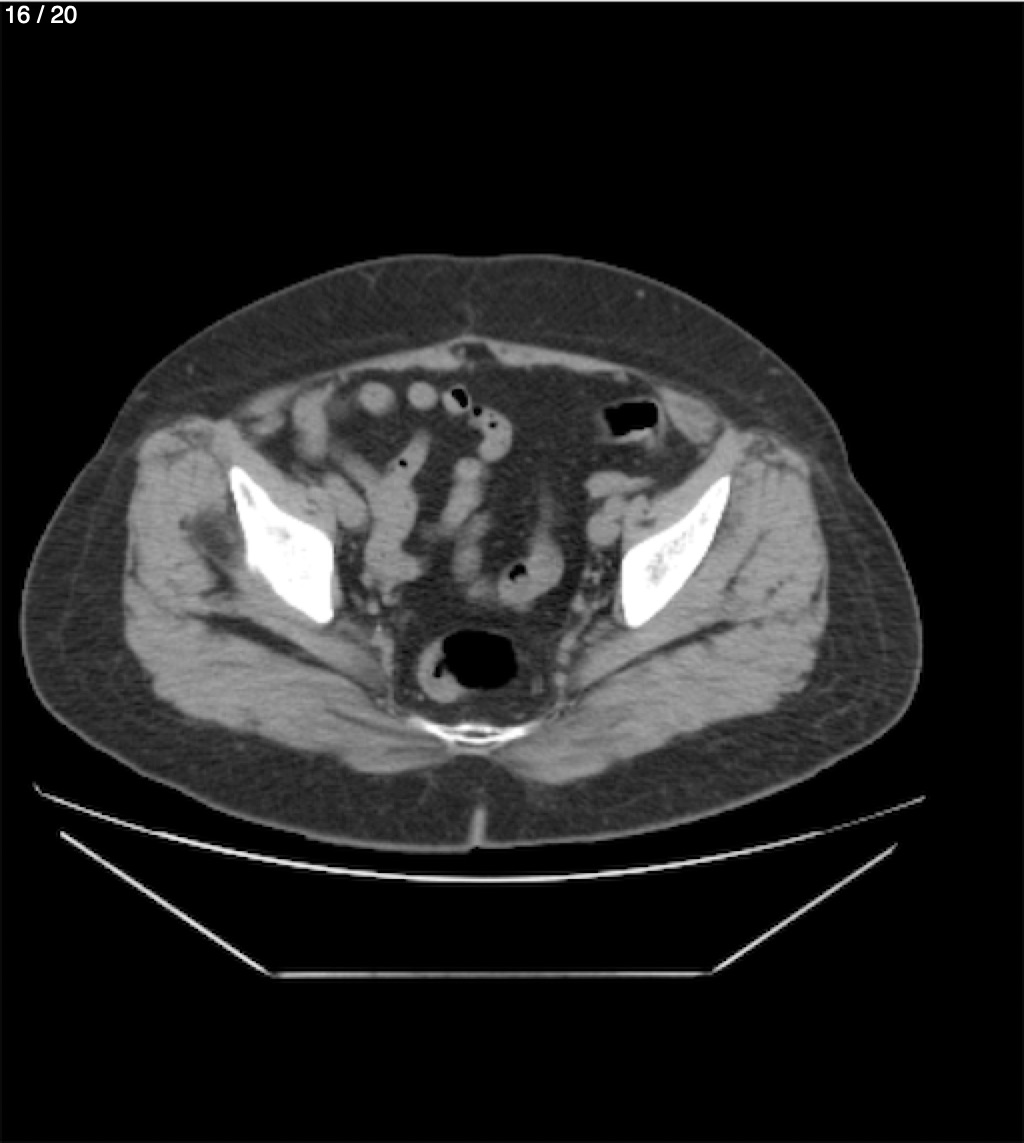

Maria Enrique Giron Dominguez63A - T.C Abdomen Simple